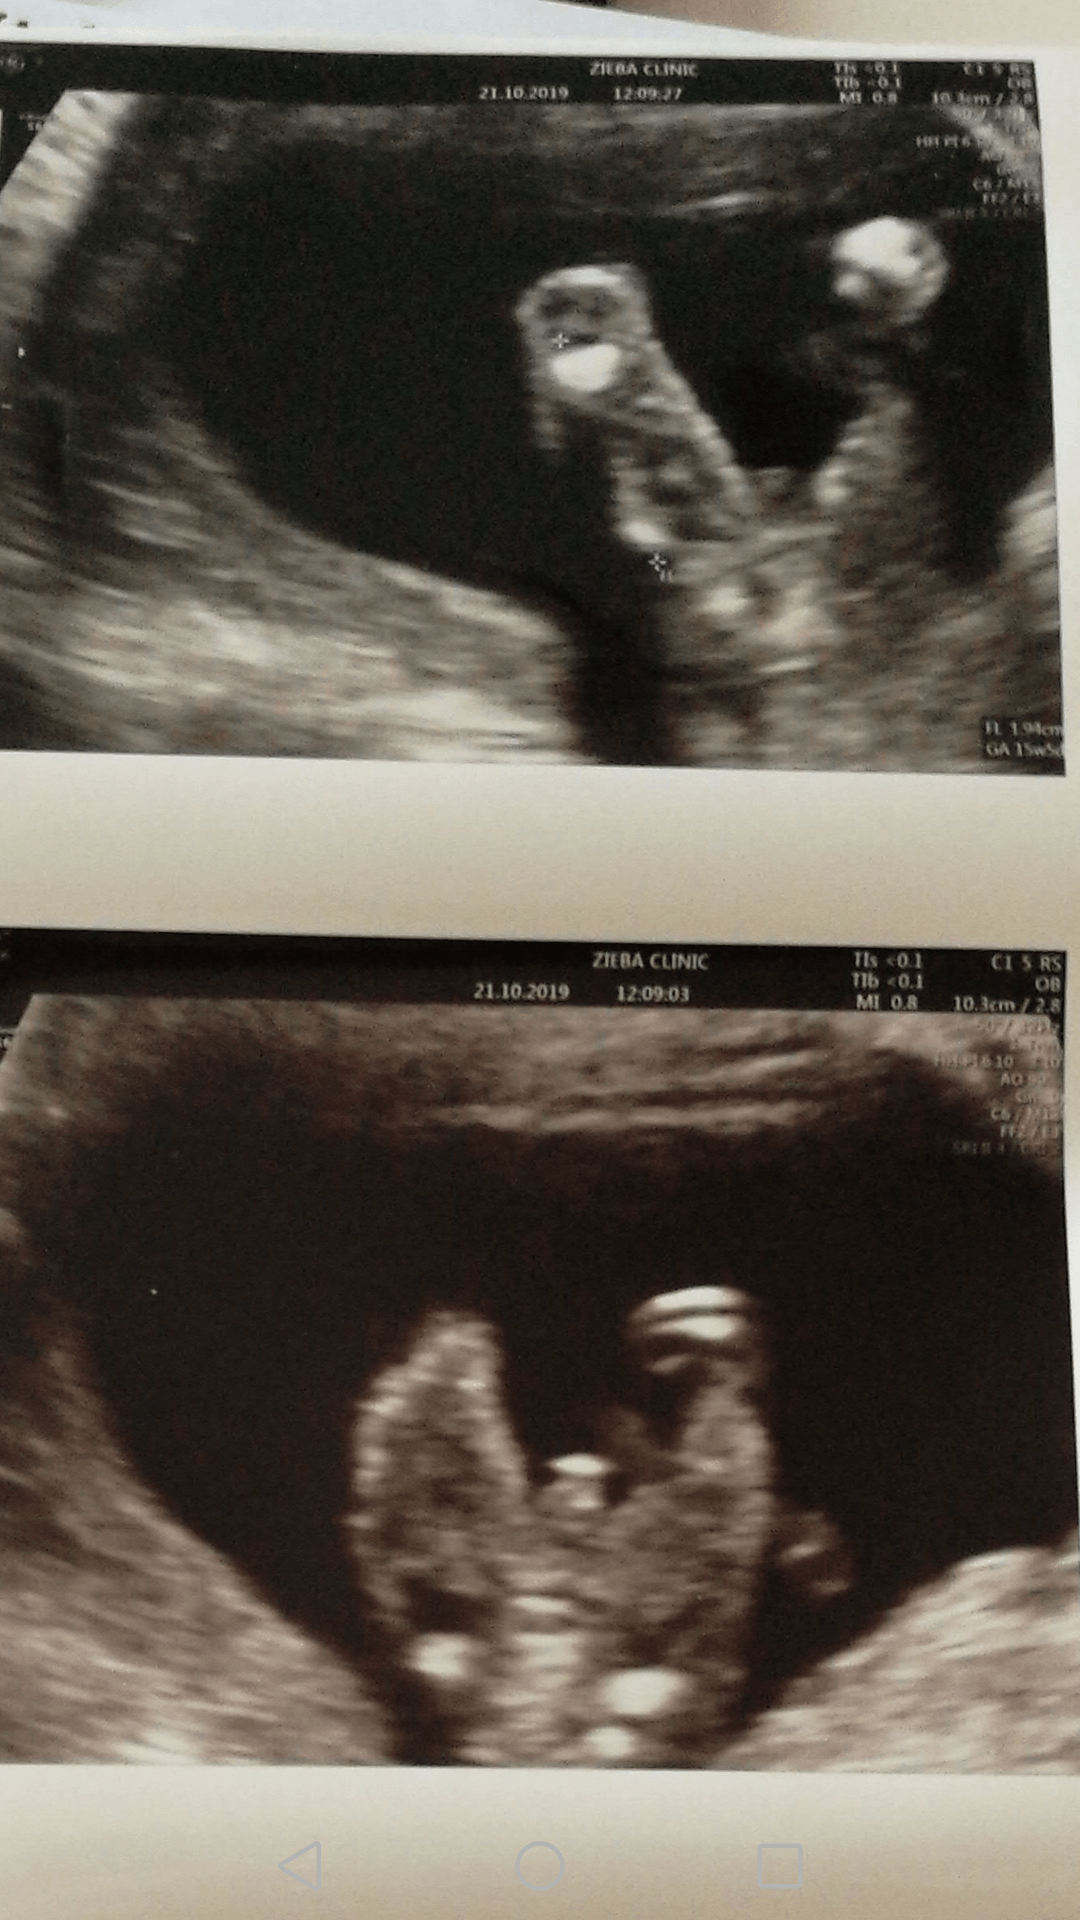

Usg chłopak czy dziewczynka

Witam w 19 tygodniu ciąży dowiedziałam się ze będę miała dziewczynkę w 20 tyg okazało się jednak , że to chłopak. Sama już nie wiem bo na jednym usg widać na pewno dziewuche a na drugim chłopca. Może to pempowina ?? Może ktoś mi pomoże rozwiązać ta zagadkę

Załączniki

• 4A8F5FF1-76CA-4DE0-AC12-5EDF08E820F2.jpg

4A8F5FF1-76CA-4DE0-AC12-5EDF08E820F2.jpg

596,4 KB · Wyświetleń: 44 122